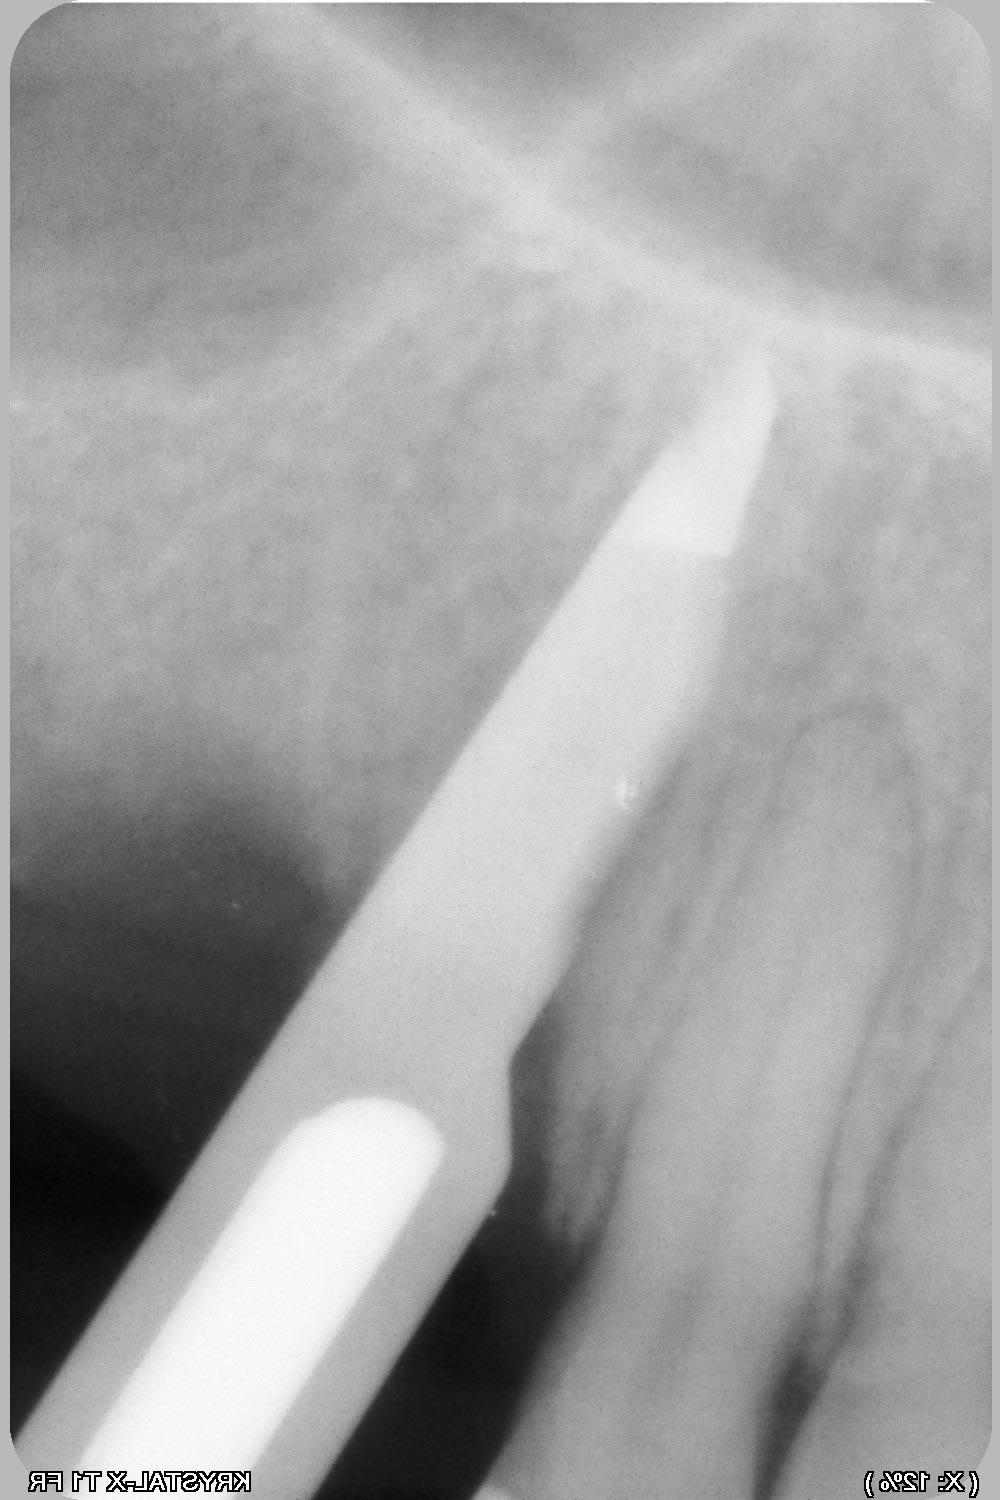

une petite idée du cas, je vais essayer en expansion, puisque c'est mon dada :-)) , et ça permettra de rajouter une vidéo pour pour animer la formation « Expansion Osseuse » à Sallanches les jeudi 4 et vendredi 5 avril 2019 ...

Be ve 23 overview nlkzvu - Eugenol

Be ve 23a 3d muwugo - Eugenol

Be ve123b overview yzsmc3 - Eugenol

Be ver 23 3d sulv8f - Eugenol

Bonjour pour obtenir ton os en vert tu as réalisé une segmentation dans bsp?

c'est pas Blueskyplan....c'est Simplant...